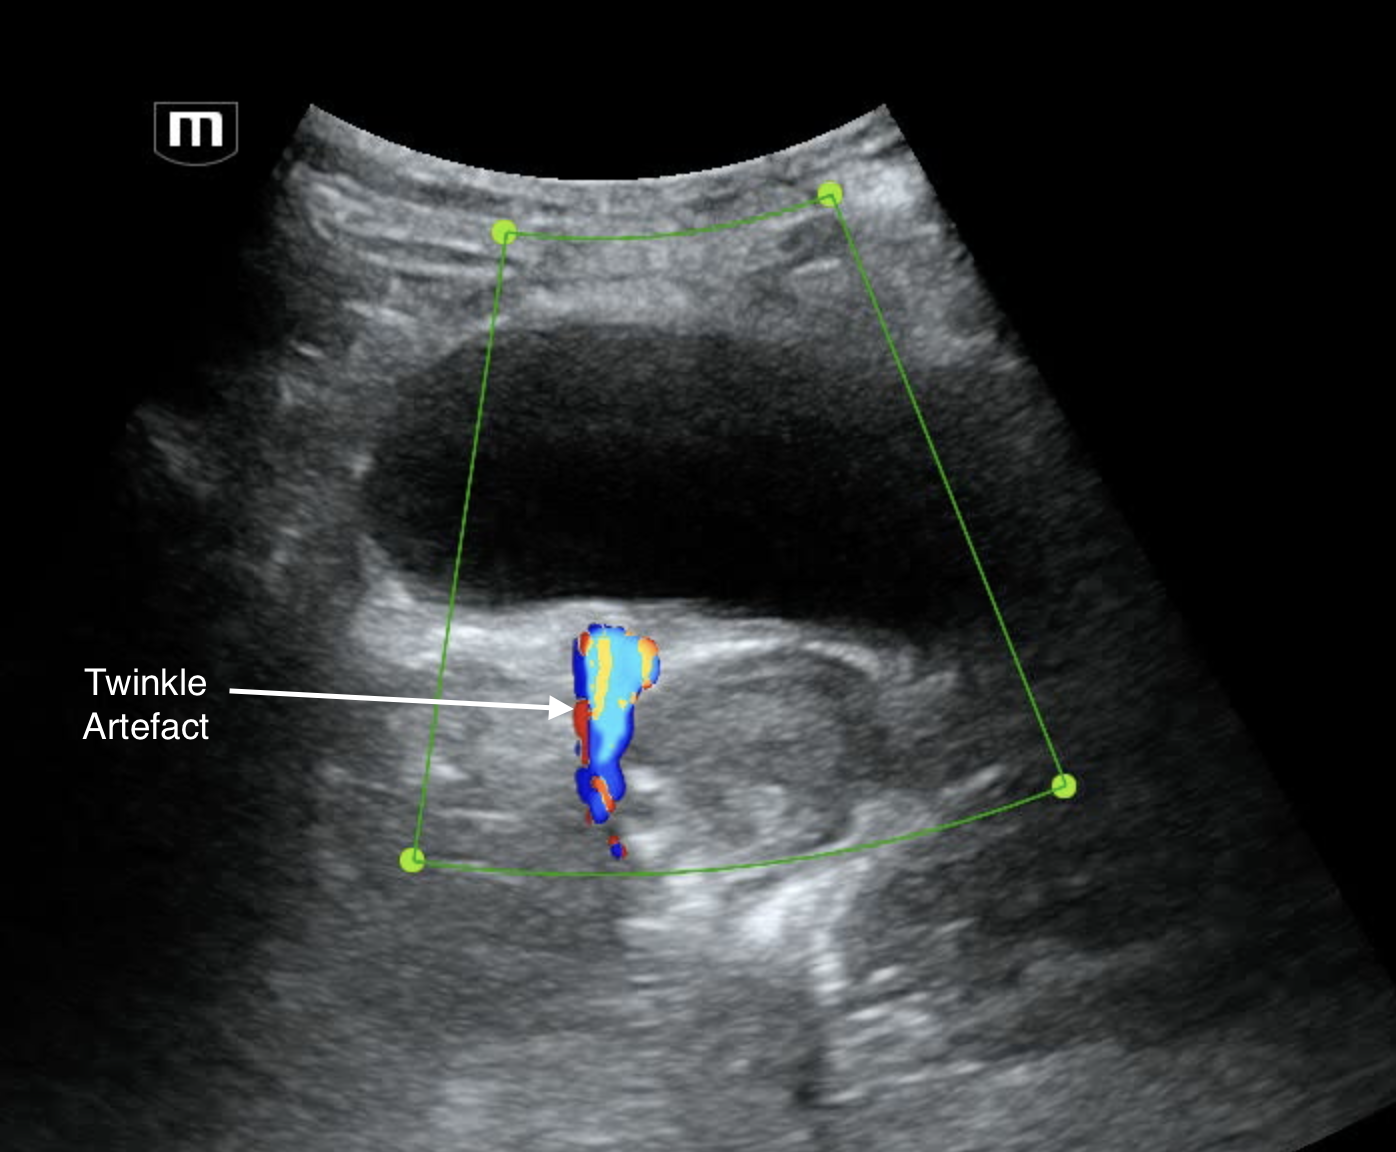

Examination of the bladder revealed a small hyperechoic linear structure at the VUJ (likely renal stone). Colour doppler on this revealed twinkle artefact which is typical for renal stones.

Pelvis (trans) showing R VUJ stone with twinkle artefact - annotated below

Intraureteric stones are typically seen best at the PUJ or the VUJ with ultrasound. The midureter is usually obscured by bowel gas. Ureteric stones are usually hyperechoic and colour doppler reveals a tail of vibrant colour reveberation artefact called the "twinkle" artefact. Often at the VUJ, the stones are small and blend in with the bladder muscle so decreasing gain to make the soft tissue hypoechoic and adding colour can increase your sensitivity. A full bladder also helps.

Pelvis trans: hyperechoic stone in R VUJ

Note that the measured size of a stone on US is usually unreliable.